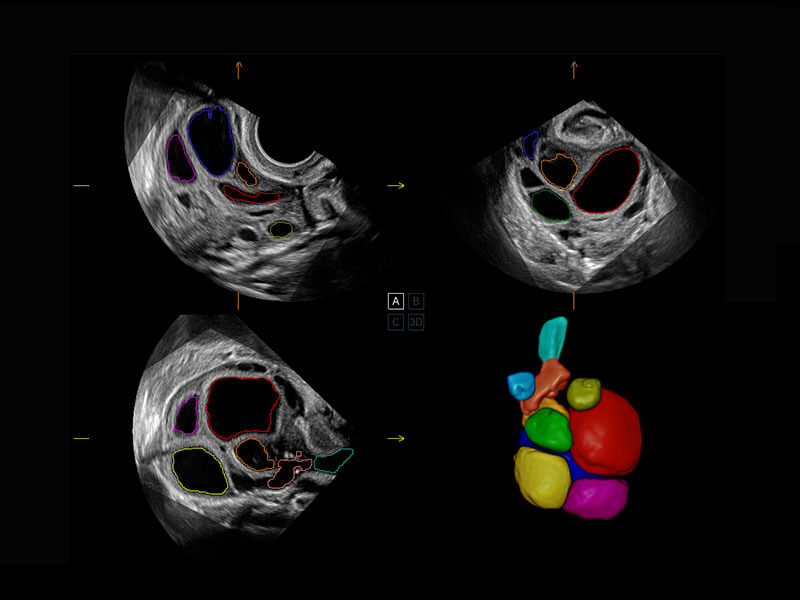

胎心筛查

P60搭载一系列胎儿心脏成像技术,实现精细的胎儿心脏评估。

• 胎心容积成像

• 新生儿心脏